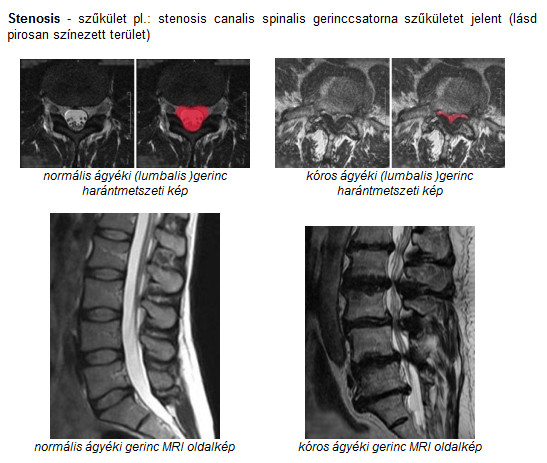

A Gerincbetegsegek Okai Es Tunetei